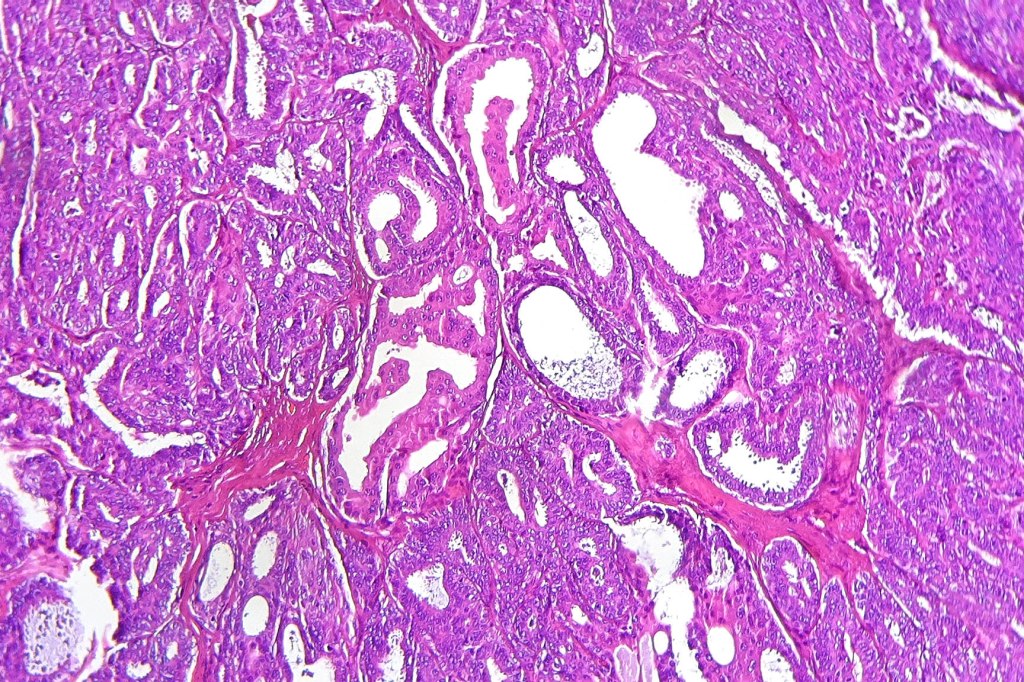

Histological features

•Circumscribed intradermal/lamina propria nodule

•Cystic or solid

•Papillae lined by myoepithelial cells with overlying epithelial cells with eosinophilic cytoplasm showing decapitation secretion

•Cribriform pattern sometimes evident